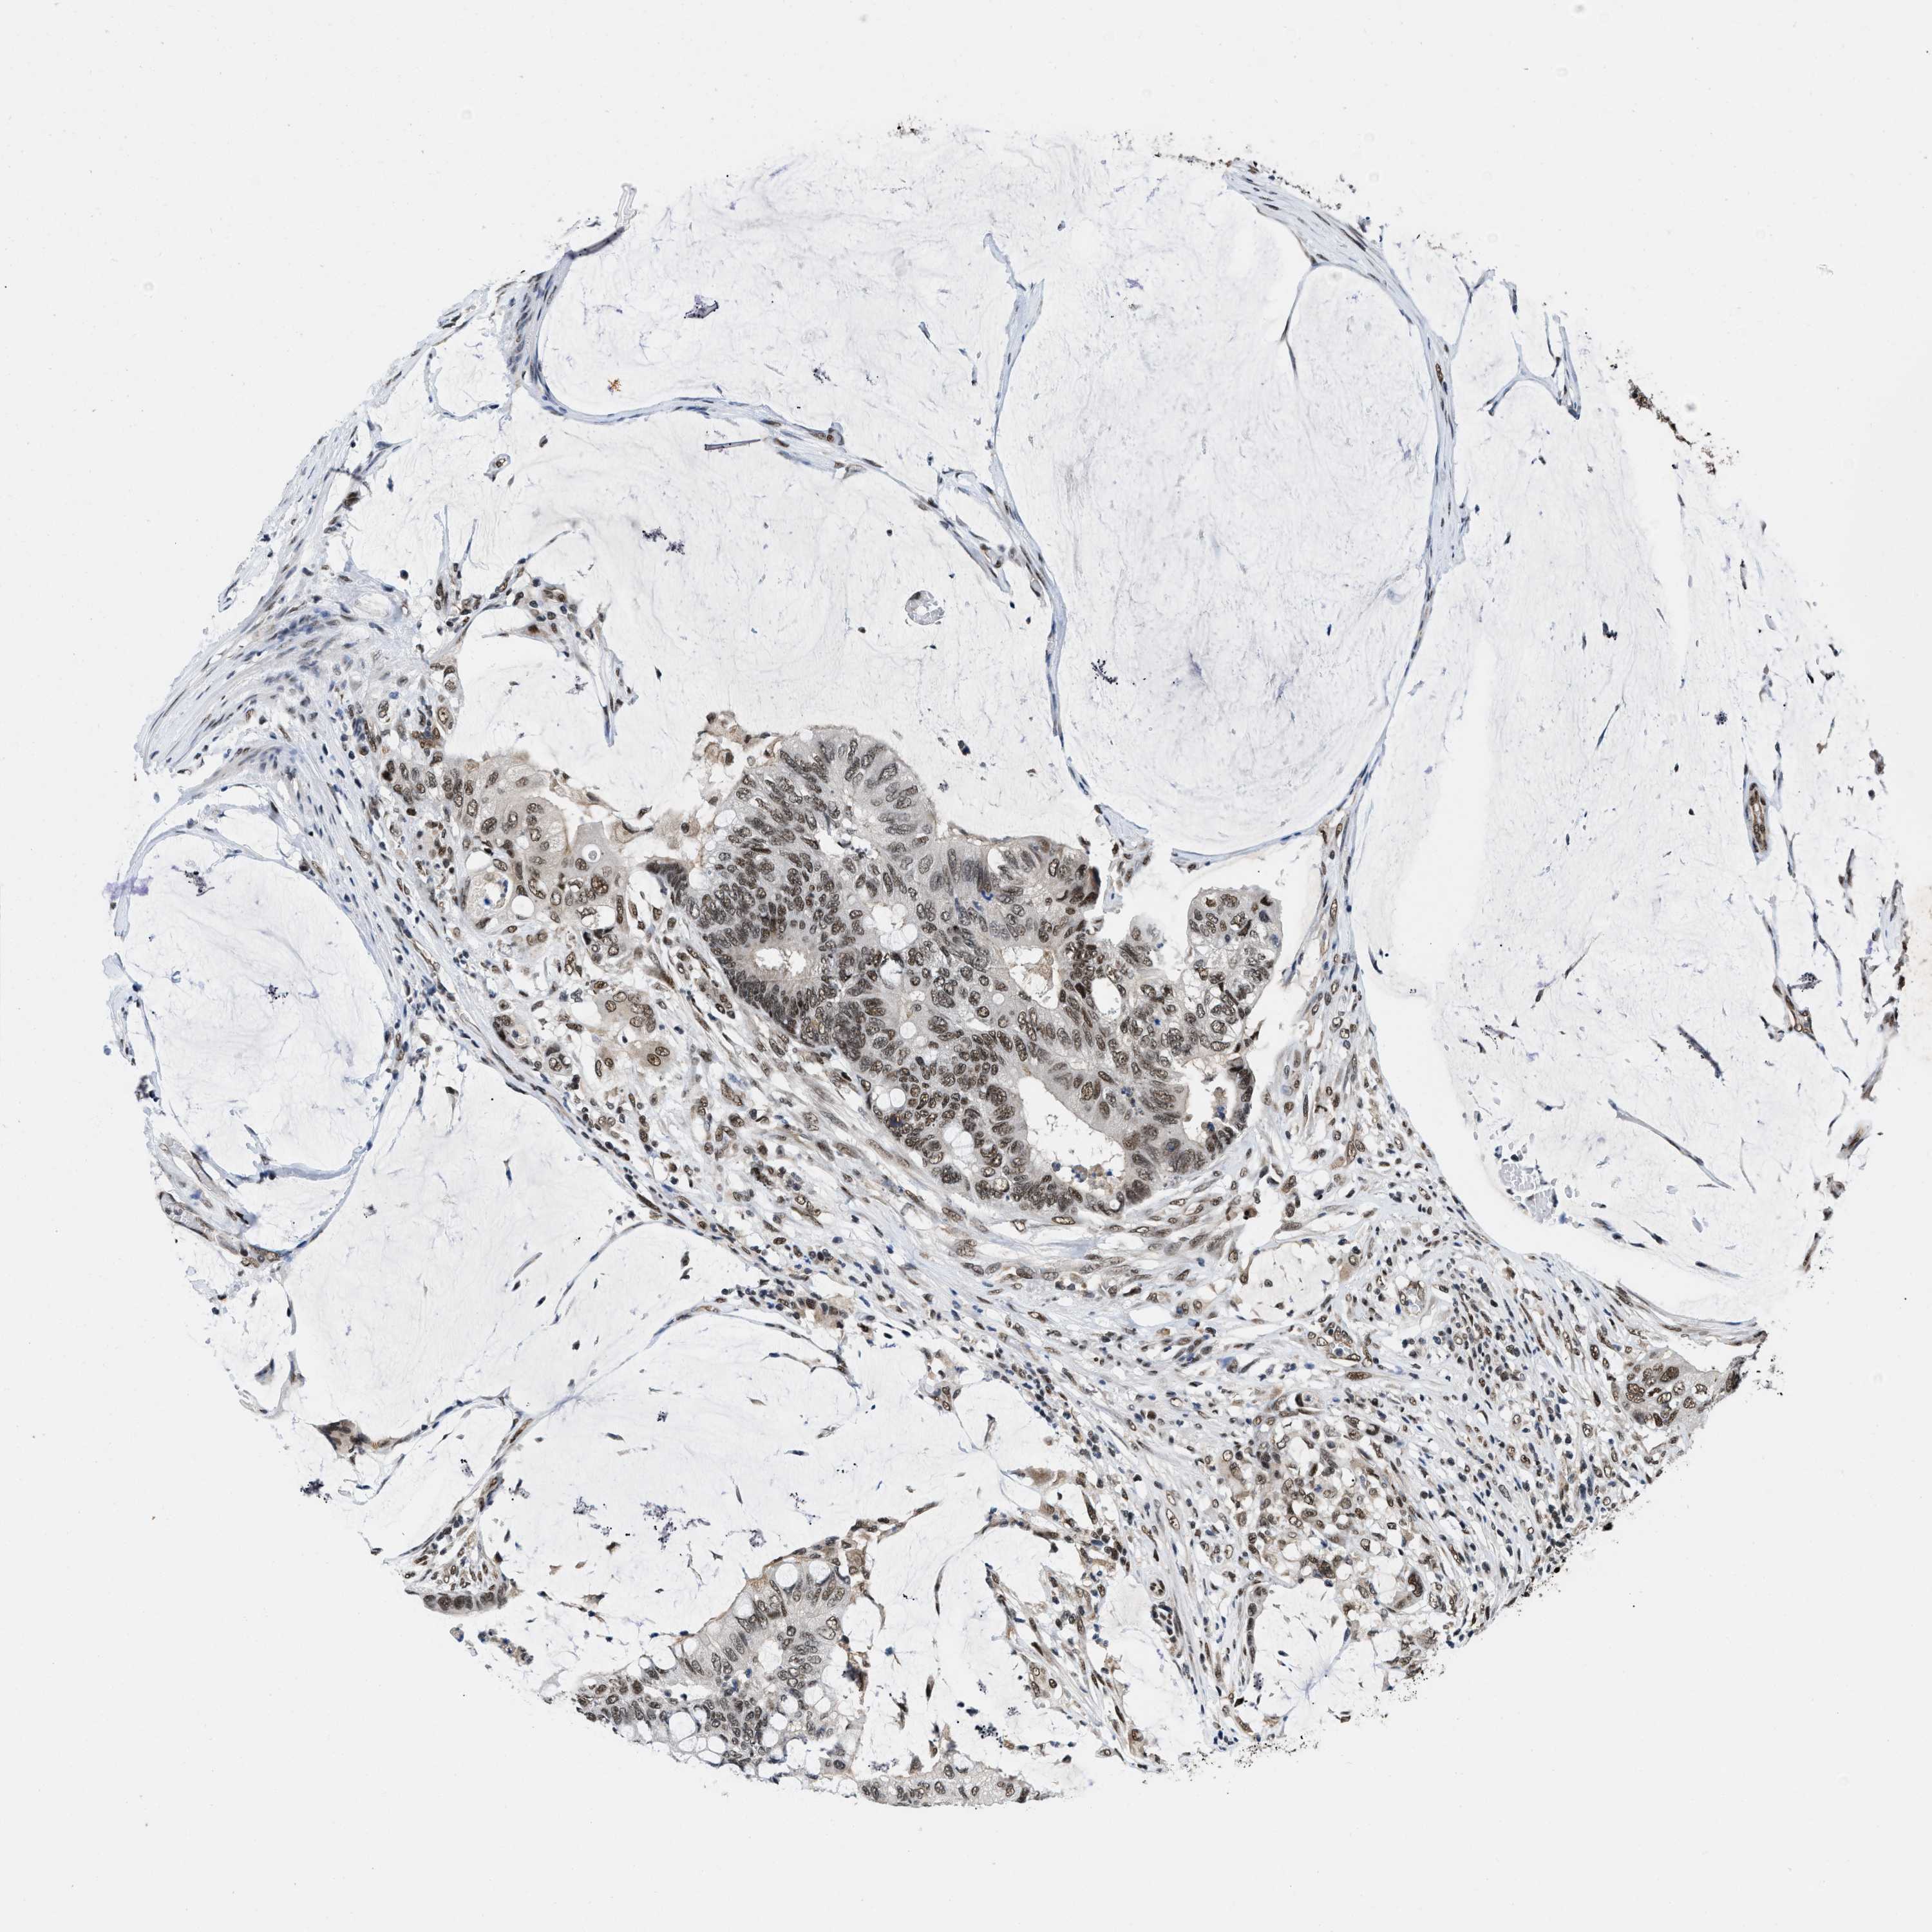

CANCER COLORECTAL CANCER Show tissue menu

Colorectal cancer

Human cancer